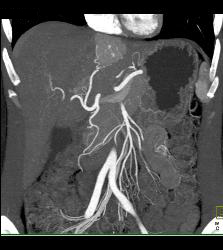

Focal Nodular Hyperplasia (FNH)